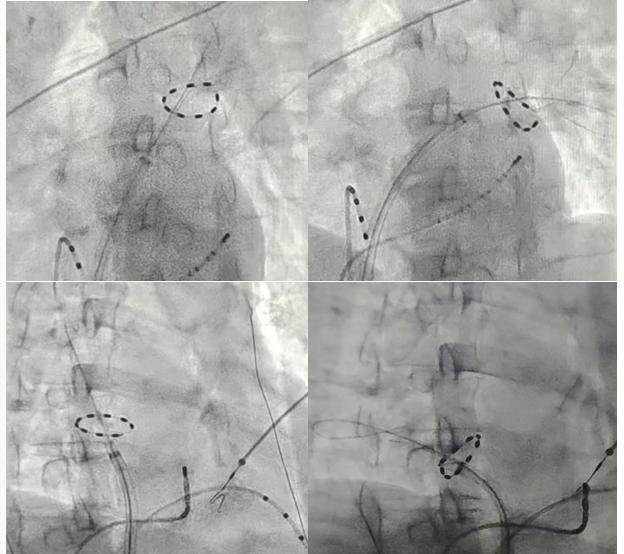

脉冲消融导管置于4根肺静脉前庭处进行脉冲消融

一年前,频繁的房颤发作让唐先生饱受心慌、胸闷折磨,服用的抗心律失常药物也收效甚微。几经辗转,唐先生来到湖南省人民医院心血管内科就诊。心血管内科的唐毅副主任医师在经过充分的评估和与患者知情确认后,选择脉冲消融术为其治疗。在心血管内科主任潘宏伟的指导下,唐毅副主任医师为患者开展了我院首例PulseSelect脉冲电场消融。术中,使用脉冲电场消融导管分别在患者四根肺静脉进行消融,仅用40分钟便彻底消除异常电信号,术后第二天患者即可下床活动。

“脉冲电场消融术就像心脏手术中的‘智能导弹’,和传统的热消融或冷消融完全不同。”唐毅副主任医师介绍,它最大的特点是既精准又安全——通过特殊的电脉冲只针对有问题的心肌细胞进行治疗,不会伤到旁边的食管、神经这些重要组织,大大降低了手术风险。且速度特别快,微秒级的高压电脉冲瞬间破坏心肌细胞膜,精准阻断异常电信号,像处理一根肺静脉最快只要2-3分钟,整体手术时间大幅缩短